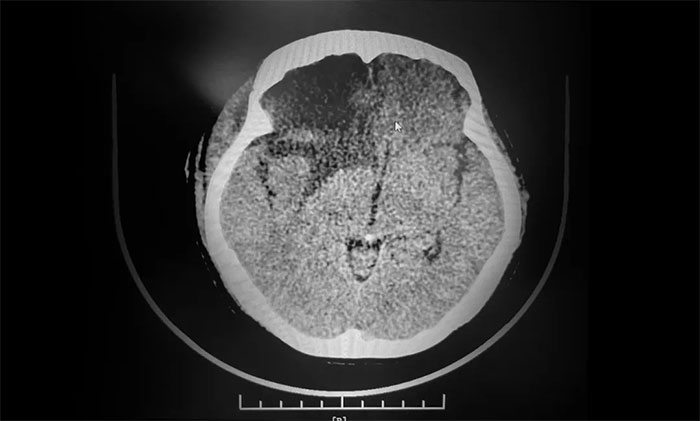

▲ 術(shù)后影像,腫瘤已切除